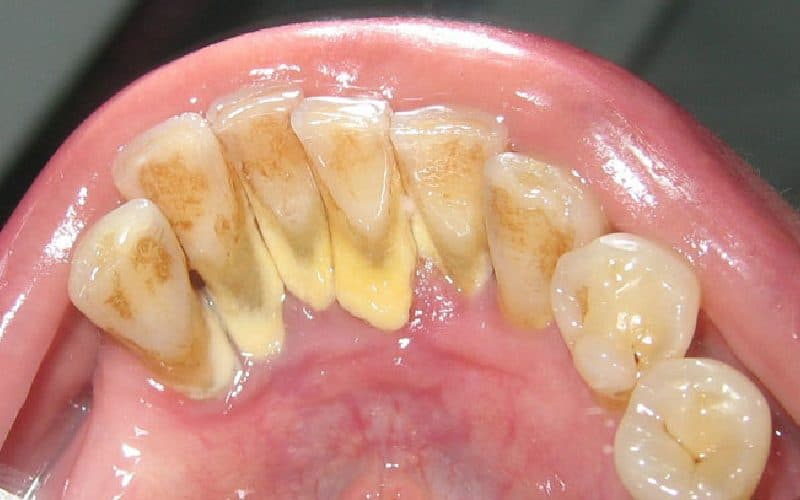

Cao răng không đơn giản chỉ là vết ố trên răng. Đó là một lớp cặn cứng, có màu từ vàng nhạt đến nâu đậm, bám chặt vào bề mặt răng và khu vực dưới nướu. Sự hình thành của nó bắt nguồn từ quá trình tích tụ và đông cứng của mảng bám – một hỗn hợp gồm vi khuẩn, protein trong nước bọt và cặn thức ăn.

Cao răng sau khi hình thành không thể làm sạch bằng các phương pháp thông thường

Khi cao răng đã hình thành, các chuyên gia nha khoa cho biết: việc loại bỏ nó bằng cách đánh răng thông thường là điều không thể.